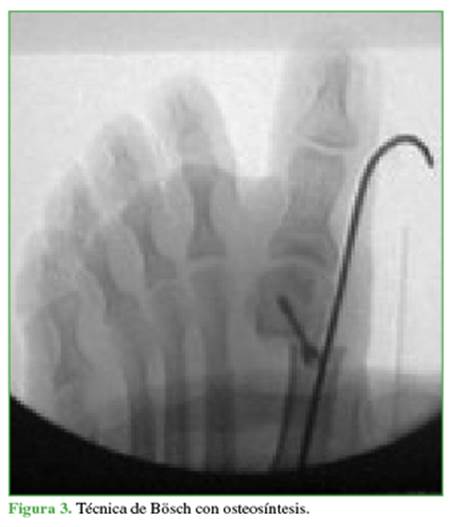

Resumen de la técnica MICA

Asocia una osteotomía en Chevron percutánea a través de un portal medial distal metatarsiano con una fresa Shannon larga y de forma extrarticular; y una osteotomía percutánea de Akin con fresa Shannon corta. El corte metatarsiano debe ser orientado inicialmente con un ángulo plantar de 10°, y luego realizar las dos ramas (plantar y dorsal). Se estabiliza la osteotomía metatarsiana luego del deslizamiento lateral de la cabeza, con dos tornillos canulados doble rosca largos paralelos, desde la metáfisis proximal del metatarsiano hacia la cabeza del mismo hueso (Figura 4); y eventualmente la Akin con un tornillo canulado.